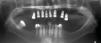

Con los anteriores procedimientos, se obtiene a los seis meses un proceso alveolar lo suficientemente amplio en longitud y en espesor (Figura 18), permitiendo la colocación de ocho implantes intraóseos (Figuras 19y20).

Después se coloca una prótesis fija total implanto soportada de zirconio-cerámica con una evolución de cuatro años, reconstruyendo el proceso alveolar en altura como en espesor a largo plazo, cumpliendo el objetivo quirúrgico así como las expectativas estéticas de la paciente (Figuras 21 a 23).